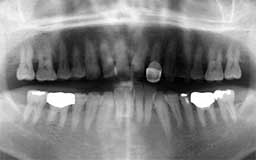

★ Pさん 52歳

年齢層をもう少し下げてみましょう。Pさんは来院時が52歳で、親知らずを除く喪失歯が

1本もなく健全そうにみえました。Oさん同様治療終了後の数年間にブランクがありました。

今から14年前の来院時にはメインテナンスを行うことの大切さがかなりはっきりわかってい

ましたので、それまでの経過を踏まえて少し強引にメインテナンスを勧めました。それ以降

はほとんど途切れることなくメインテナンスを継続されています。右の上顎第一大臼歯の1/3

だけ抜歯(ヘミセクション)していますので正確には現在残存歯数は27本と2/3ということ

になりますが、補綴(ほてつ)物も少なく10年後が楽しみな患者さんです。

| Pさん 初診時 52歳 男性 歯周疾患の進行傾向が随所に認められるが、年齢の割には比較的良好 |

Pさん 20年後 71歳 清掃状態は決して良好とはいえないが、20年間毎月メインテナンスを継続し良好な状態を保っている |